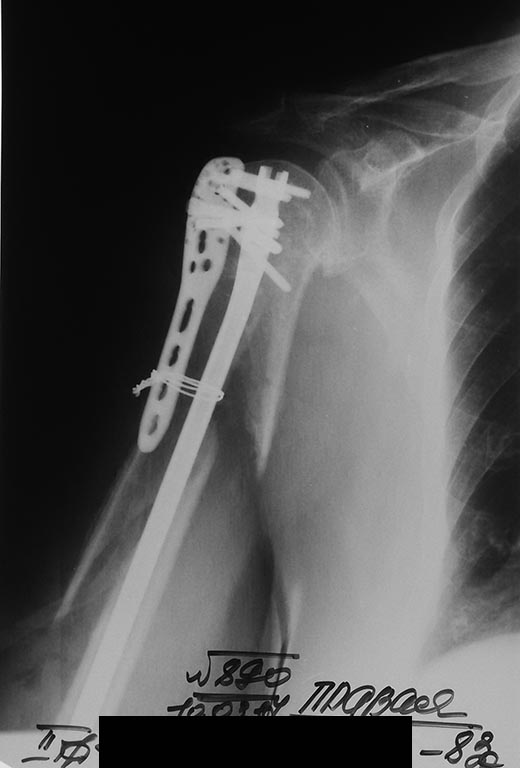

[Ortho] Периимплантный перелом плеча

Таков результат. Раны зажили первично. Пациентка выписана без

иммобилизации. Буду наблюдать в динамике. Жду комментариев.Коллеги.